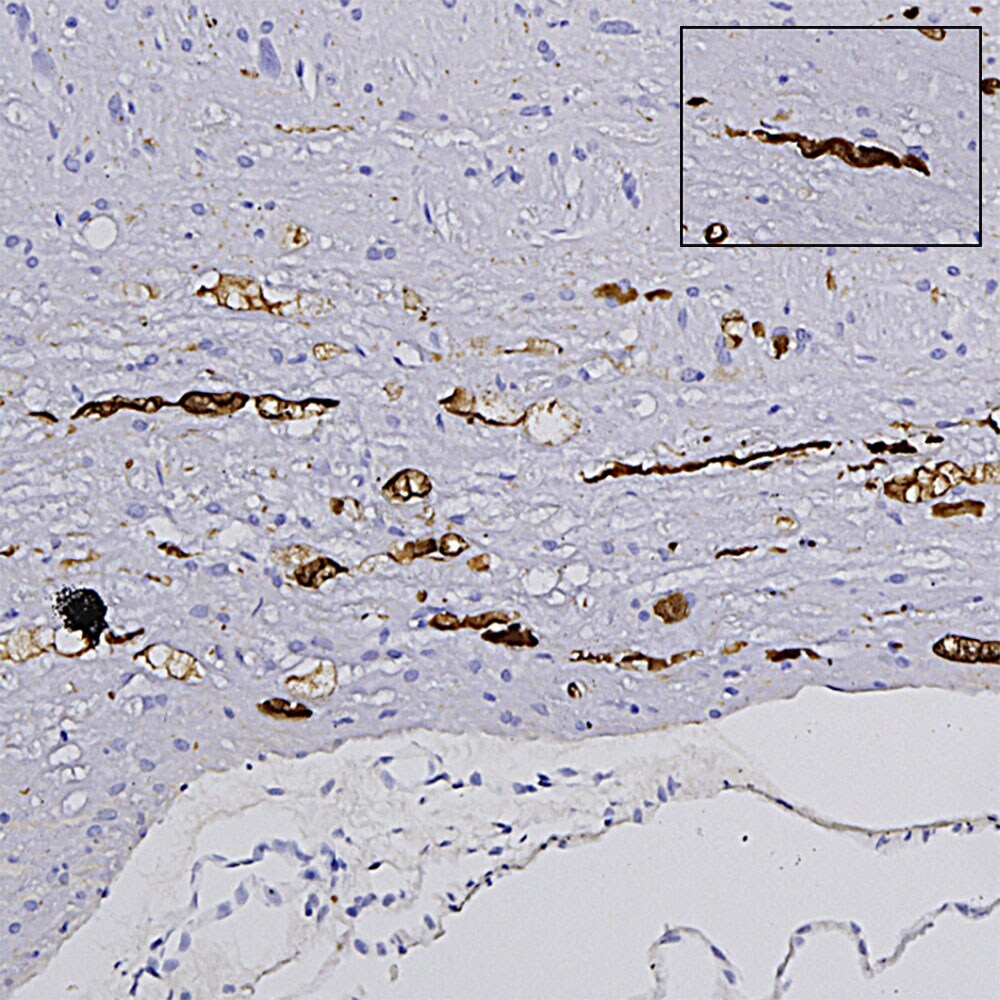

- Chromogenic immunohistochemistry of NEFL in formalin fixed paraffin embedded brain stem section from a transgenic mouse model of ALS. Samples were stained with NEFL monoclonal antibody (Product # MA5-47382) using a dilution of 1:1,000. Detected in DAB (brown) following the Vector LabsM.O.M.® ImmPRESS® HRP method, without the antigen retrieval step. Hematoxylin (blue) was used as the counterstain. The NEFL antibody labels what are clearly degenerated axons, showing typical swollen, sinusoidal and discontinuous profiles. Note that under these conditions healthy axons are not stained.